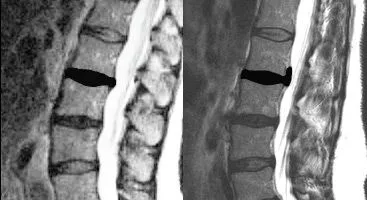

Severe Disc Herniation Lumbar Spine

Amy was loading her washing machine when she bent over to pick up a laundry basket. She felt something “go out” in her lower back and experienced an intense pain that began radiating down her left leg.